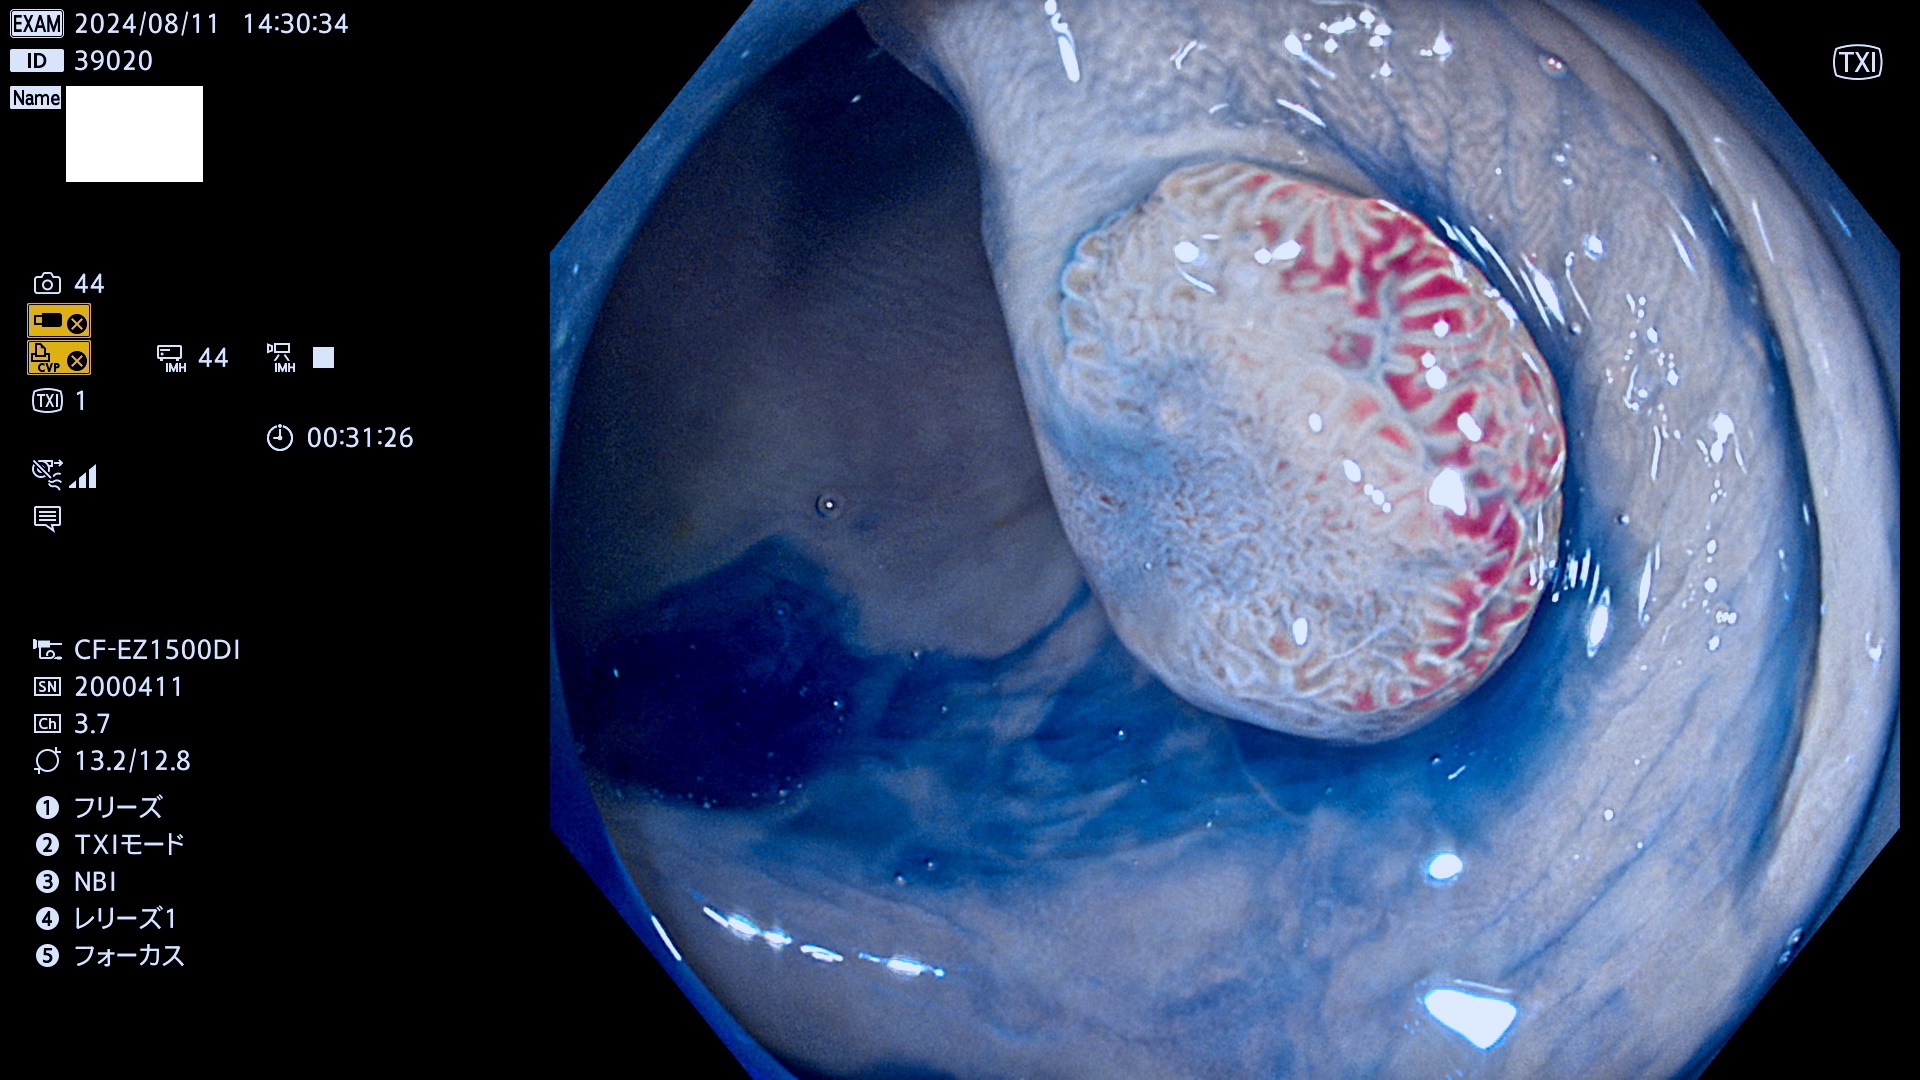

今週のUb、Uc型腺腫

完全に平坦な物をUb、陥凹している物をUcと呼びます。最も発見が難しく危険な病変です。

毎週の検査(木・金・土・日)に発見されたUb、Uc型・腺腫を、その週の日曜の夜にUPし1週間、提示します。

抽出の対象期間 2024年8月8日〜8月11の4日間(30件の検査)11件 (11/30=35%)